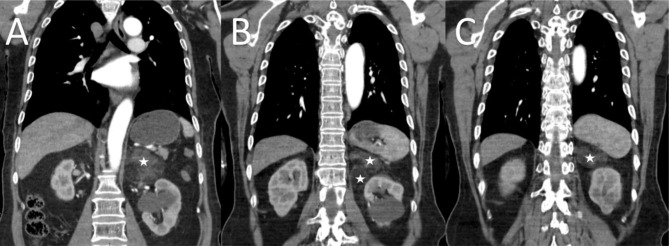

The patient underwent radical thyroidectomy due to papillary thyroid carcinoma and took levothyroxine. He had been under follow-up with an endocrinologist regarding this issue. On one of his visits to the endocrinologist, calcium, phosphorous, and hormonal assessment alongside neck, chest and mediastinum, and abdominopelvic computed tomography (CT) scan was ordered to be performed. In the blood test, calcium, phosphorous, T4, antithyroglobulin antibody, and thyroglobulin were within the normal range, but thyroid-stimulating hormone (TSH) was 0.05 (reference range: 0.27–5.95). Also, 24-hour urine levels of cortisol, vanillylmandelic acid (VMA), metanephrine, and normetanephrine, measured to exclude the presence of a possible pheochromocytoma, were within the normal range. However, in the abdominopelvic CT, a well-circumscribed fat-containing 78 × 61 × 65 mm bi-lobulated mass was detected in the left adrenal fossa, resulting in inferior and posterior displacement of the left kidney. The first differential diagnosis was myelolipoma. Besides, no enhancing nodule or solid part was seen (Fig. 1). The patient was then referred to our clinic for a mass excision. He was asymptomatic and was scheduled to undergo laparoscopic-assisted adrenalectomy.

Fig. 1.

Coronal section of preoperative computed tomography (CT) scan; (A) anterior mass, (B) both masses, (C) posterior mass